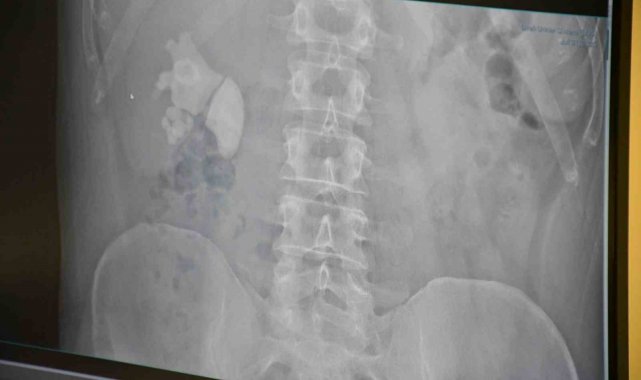

Yozgat'ta yaşayan 45 yaşındaki Serhat Evran'ın böbreğinden 100'e yakın taş çıktı.

Akdağmadeni ilçesinde yaşayan Serhat Evran doktorları bile şaşırtan sağlık problemiyle karşı karşıya kaldı. Şiddetli böbrek ağrısı şikayetiyle Yozgat Şehir Hastanesi'ne başvuran Evran'ın detaylı tetkiklerinin yapılmasının ardından böbreğinde 100 taneye yakın taş tespit edildi.

Ameliyatı gerçekleştiren Op. Dr. Fatih Kocamanoğlu ve Op. Dr. Arif Bedirhan Bayraktar hastanın son durumunu kontrol ederek kısa sürede taburcu olacağını söyledi. Hastanın durumu hakkında açıklama yapan Op. Dr. Fatih Kocamanoğlu hastanın 10 yıl kadar önce sağ böbrekten taş cerrahisi operasyonu geçirdiğini ifade etti. Kocamanoğlu, "Yaptığımız incelemede sağ böbreğin tamamını dolduran taşları vardı. Hastayla görüşerek bu tür büyük taşlarda büyük bir cerrahi olabileceğini ve hastanın birkaç delikten girerek, sırttan delerek ameliyat yapılması gerektiğini söyledik. Hastamız kabul etti. Çarşamba günü hastanın ameliyatını yaptık. Tek delikten girerek neredeyse tamamını temizledik. Bugün de hastamızı sağlıklı bir şekilde taburcu edeceğiz" dedi.